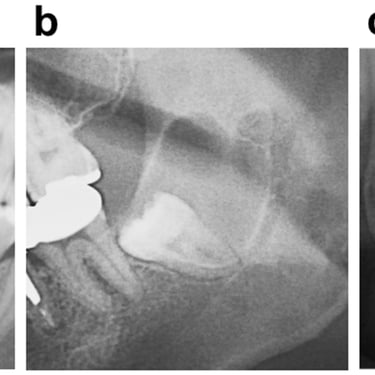

Extracción de Muelas del Juicio

La extracción de las muelas del juicio es un procedimiento quirúrgico para remover los terceros molares que pueden causar dolor, infección o daño a otros dientes debido a su posición o crecimiento anómalo.

Los pacientes pueden experimentar dolor, hinchazón y, en algunos casos, infección alrededor de estas muelas.

El tratamiento incluye la extracción quirúrgica para prevenir o resolver complicaciones.